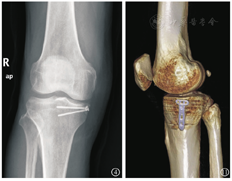

病例1 患者男,52岁,因"机器压伤致左大腿、右膝疼痛活动受限12 h"于2018年1月入院。入院查体:左侧大腿肿胀压痛,畸形,右膝关节肿胀压痛,活动受限,双下肢肢端血供感觉正常,由于疼痛查体欠配合。入院完善左侧股骨正侧位X线、右膝X线(图1)、CT(图2)及MRI(图3),诊断"左侧股骨干骨折、右侧反式Segond骨折"。为控制创伤,行分期手术。入院7 d后患者一期行"左侧股骨干骨折切复内固定术",术后恢复可。入院14 d行右膝关节镜辅助下内固定手术。麻醉下查体提示右膝关节30°外翻试验阳性,前后抽屉及Lachman试验阴性,术中常规行关节内血肿清理后发现前后交叉韧带无损伤,内侧半月板(medial meniscus,MM)撕裂予半月板成形,内侧撕脱骨折位于内侧半月板后角下方并向内侧移位,关节镜监视下克氏针体外定位骨折位置后取膝关节内侧2 cm切口纵行劈开内侧副韧带分离至骨折处,见骨折块约1.5 cm×1 cm×1 cm大小并翻转,在关节镜监视下复位骨折后用2枚3 mm空心钉固定,再可吸收线连续缝合修补内侧副韧带(medial collateral ligament,MCL),术后复查右膝X线(图4)示骨折解剖复位。术后常规佩戴可调节膝关节支具伸直位固定并行直腿抬高锻炼股四头肌,术后4周开始膝关节0°~90°屈曲活动,术后6周膝关节0°~120°屈曲活动并拄双拐保护下开始部分负重,术后10周膝关节完全负重并达到正常活动度。目前术后半年,查外翻试验转阴,日常生活无不适,能慢跑,打羽毛球,右膝无不稳感,Lysholm评分90分。

病例2 患者男,50岁,因"摔伤致右膝关节疼痛3 d"于2019年2月入院。入院查体:右膝关节肿胀压痛,活动受限,肢端血供感觉正常。入院查右膝CT(图5)及MRI(图6)提示右膝后交叉韧带止点无移位骨折,胫骨平台内后缘撕脱骨折累及内侧副韧带深层,诊断"反式Segond骨折"。完善术前准备后行右膝关节镜手术,麻醉下查体示右膝关节肿胀,前后抽屉及Lachman试验阴性,内外翻试验阴性。术中清理血肿后探查前后交叉韧带完整,后叉止点骨折无移位,发现内侧半月板后角撕裂行内侧半月板成形,内侧撕脱骨折块位于内侧半月板下方并翻转,细针定位骨折块位置后取膝关节内侧3 cm切口,分离至骨折部位,见骨折块菲薄约1 cm×0.5 cm×0.3 cm,连及内侧副韧带深层,考虑骨块太小空心钉固定困难改用缝线捆扎,复位后在关节镜监视下在骨折块前外及后外建立2 mm骨隧道,用硬膜外导针过线,将2号爱惜绑线捆扎复位骨折块,平台内侧放置小T型钢板作为阻挡支撑,将爱惜绑线打结在钢板上,术中关节镜探查骨折解剖复位(图7,图8,图9,图10)。术后复查CT进一步证实示骨折解剖复位(图11)。术后常规佩戴可调节膝关节支具伸直位固定并行直腿抬高锻炼股四头肌,术后2周开始膝关节0°~90°屈曲活动,术后6周膝关节0°~120°屈曲活动并拄双拐保护下开始部分负重,术后10周膝关节完全负重并达到正常活动度。术后半年复查,患者右膝无疼痛,能慢跑,Lysholm评分95分。

以往对于反式Ssegond骨折的报道更多见于放射学领域,而在骨科手术领域的报道寥寥无几[6,7,8,9]。由于反式Segond骨折合并膝关节韧带损伤,因此以往的治疗方案也只关注膝关节多发韧带损伤及脱位,而忽视了骨折本身的治疗。对于反式Segond骨折本身缺乏有效的治疗指南,也没有具体手术方法的描述。结合文献,对于反式Segond骨折块是否需手术治疗主要从骨折块的大小、位置及功能几个方面考虑。对于骨折块远离关节面、骨块较小及未累及内侧副韧带的可选择保守治疗[3],而对于骨块位于关节面负重区、累及内侧副韧带的则需手术治疗[8,10]。手术方式可选择开放或关节镜手术,固定方法可用螺钉、钢板或缝线技术。本文2例患者的反式Segond骨折位于半月板负重区,均有移位翻转,累及内侧副韧带深层,均需手术治疗。病例1采用关节镜下螺钉固定大骨块,病例2采用关节镜下缝线联合钢板固定小骨块,均达到解剖复位,取得满意效果。关节镜辅助下的骨折内固定手术不仅可清楚观察骨折及关节内情况,也可镜下解剖复位骨折后直接缝线或螺钉固定,达到微创治疗的效果。据笔者了解,本研究是国内首次详细报道的关节镜下缝线联合钢板固定治疗反式Segond骨折的文章。